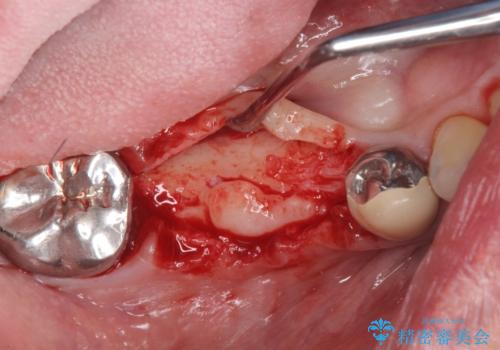

支台を増やし、残った歯の負担を減らし守るために欠損部位にインプラントを埋入し咬合力の負担に対応できる環境を整えます。

インプラント治療は、ブリッジや入れ歯と異なり人口の歯根となるインプラントを顎骨内に埋入することで咬合力に耐える支台を増やせるというメリットがあります。